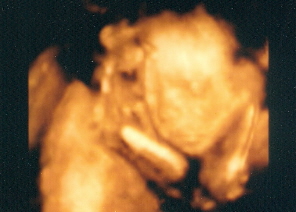

"Bélánkról" tettem fel egy képet, itt még megmutatta az arcát, de utána eltakarta a kezével, és végig ott is volt, közben nagyokat ásitott, uncsi volt neki az ultrahang.